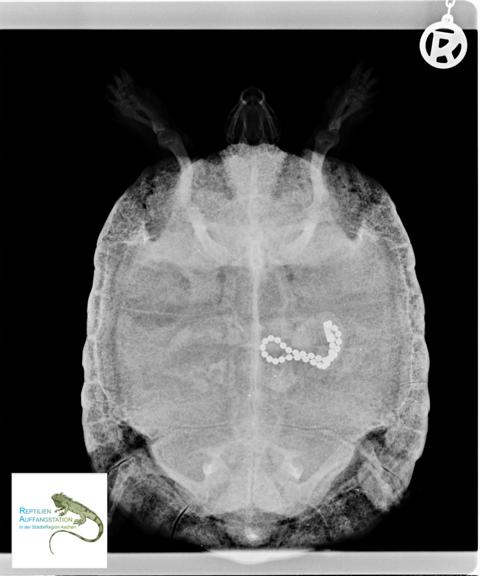

Das Blutbild zeigte (erwartungsgemäß) ausgesprochen schlechte Nieren- und Leberwerte. Das Röntgenbild zeigte ein vermeintlich noch größeres Problem. In einer Darmschlinge befand sich eine geschlossene Metall-Perlenkette, wie sie als Schlüsselanhänger verwendet wird. Offenbar hatte das Tiere die Kette vom Fußboden „aufgesammelt“ und gefressen.

Eine erste Röntgen-Verlaufskontrolle nach einer Woche zeigte keine substanzielle Bewegung der Kette. Vor einem operativen Eingriff wurde über zwei weitere Wochen versucht, die Kette auf natürlichem Wege mit dem Darminhalt zu „entsorgen“.

Eine weitere Röntgen-Verlaufskontrolle zeigte aber das gleiche Bild: die Kette hatte sich so gut wie nicht weiterbewegt. Eine Operation war somit nicht zu vermeiden. Diese wurde von einem erfahrenen Reptilienfachtierarzt vorgenommen. Im Rahmen der OP wurde deutlich, warum die Kette nicht ausgeschieden werden konnte. Der Fremdkörper war bereits eingekapselt, hatte sich allerdings am leicht geöffneten Verschluss in der Darmwand verhakt. Folglich musste besonders vorsichtig und sorgsam vorgegangen werden.